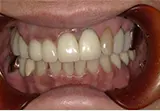

CASE

| 年齢/性別 | 40代女性 |

| 主訴 | 右上の詰め物が取れた |

| 治療内容 | 歯周病とむし歯の治療を目的に来院。左下の奥歯は根の状態が悪く、病変も大きかったため保存が困難と判断。 インプラント治療を実施しました。 |

| 治療期間 | 4か月 |

| 費用 | 566,500円税込 |

| リスク・副作用 | 炎症反応によって術後に腫れが生じることがあります。その程度は、手術の範囲や方法によって異なりますが、多くの場合、時間の経過とともに徐々に治まります。 ごく稀に、下顎奥歯の外科手術後に、唇や顎に痺れを感じることがあります。 |